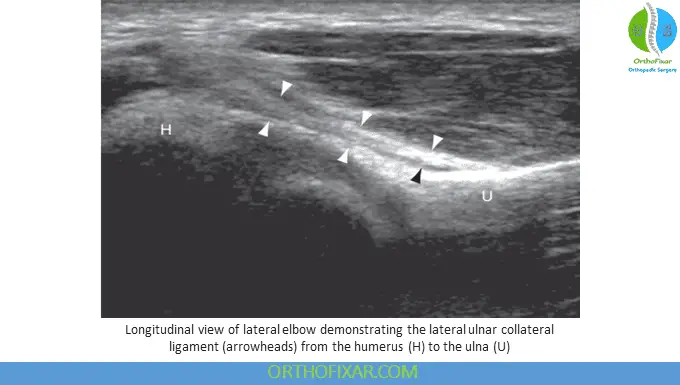

Lateral Collateral Ligament Complex

The lateral collateral ligament presents a diagnostic challenge due to its similarity in appearance to the common extensor tendon. Differentiation requires following these structures distally, where the deeper radial collateral ligament attaches to the annular ligament immediately over the radial head, while the common extensor tendon becomes increasingly muscular superficially. The lateral ulnar collateral ligament (LUCL) can be visualized by angling the transducer posteriorly from the distal humerus to the ulna, appearing as a hyperechoic, fibrillary structure.